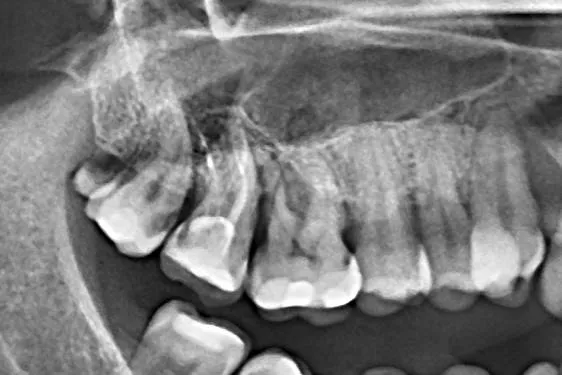

Tratament endodontic molar inferior cu elongare coronară și reconstrucție corono-radiculară Detalii caz